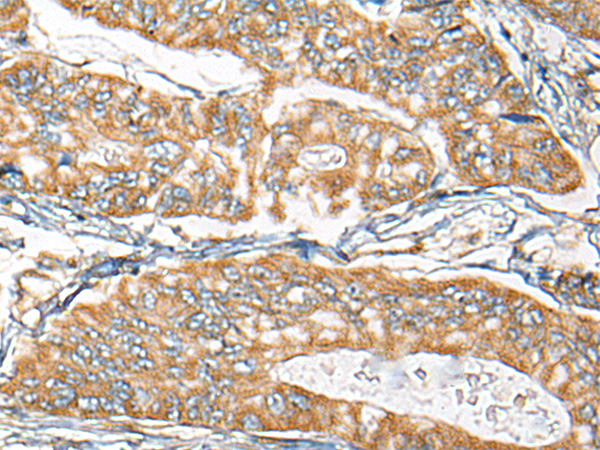

IHC positive control: |

Human gastric cancer and Human thyroid cancer |

IHC Recommend dilution: |

25-100 |